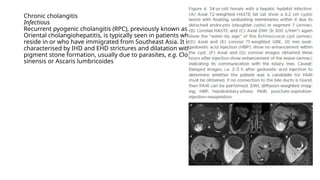

Chronic cholangitis

Infectious

Recurrent pyogenic cholangitis (RPC), previously known as

Oriental cholangiohepatitis, is typically seen in patients who

reside in or who have immigrated from Southeast Asia. It is

characterised by IHD and EHD strictures and dilatation with

pigment stone formation, usually due to parasites, e.g. Clonorchis

sinensis or Ascaris lumbricoides